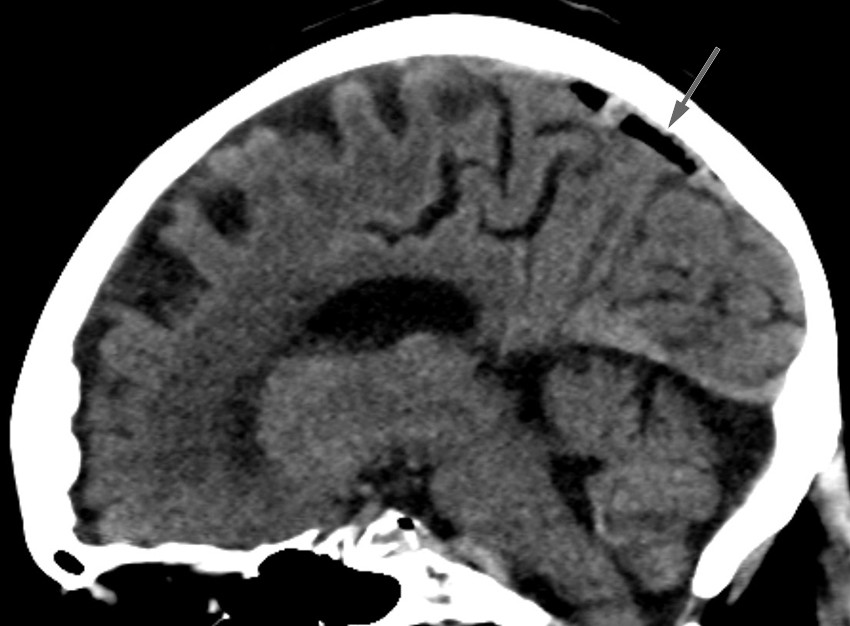

Bildet viser luft i sinus sagittalis superior, et tilfeldig funn hos en kvinne i 80-årene undersøkt med CT caput ett døgn etter fall i hjemmet med hodetraume og forbigående bevissthetstap. CT viste ingen tegn til intrakranial blødning eller skjelettskade, men det var luft i cerebrale venesinuser, mest i sinus sagittalis superior, mindre luftbobler i sinus transversus bilateralt, høyre sinus sigmoideus, sinus cavernosus og i en vene kranialt i venstre orbita. Grunnet rask atrieflimmer hadde pasienten før CT fått anlagt perifert venekateter på høyre underarm med injeksjon av to doser med 5 mg metoprolol. Pasienten hadde ingen symptomer som kunne tilskrives cerebral venøs luftembolisme.

Foreslått behandling er Trendelenburgs leie for å lede luften bort fra hodet, samt 100 % oksygen for raskere reabsorpsjon av gassbobler (2, 3). Hyperbar oksygenbehandling vurderes ved alvorlige tilfeller (1–3). Det er usikkert hvorvidt asymptomatiske pasienter bør behandles. Vår pasient fikk 100 % oksygen, men grunnet hjertesvikt ble hun ikke lagt i Trendelenburgs leie. Kontroll CT caput 13 timer etter første undersøkelse viste avtagende mengder luft. Supplerende CT cervikalcolumna/thorax var uten tegn til traumatisk skade som kunne forklare luftembolusene. Det må her mistenkes perifert venekateter som kilde, selv om traumatisk årsak ikke kan utelukkes. Pasienten hadde ikke vært utsatt for kirurgi, andre prosedyrer eller barotraume. Det ble ikke funnet avvik fra prosedyre ved gjennomgang av venekateteranleggelsen.